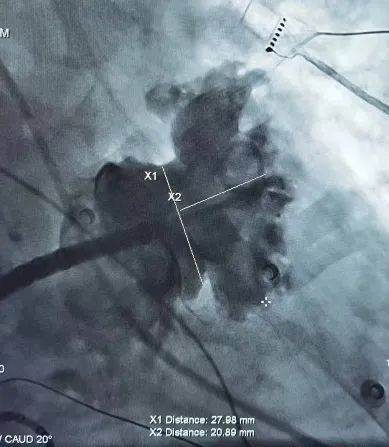

心房颤动患者容易发生脑卒中,是因为心房不能规律地收缩,血液容易在心房内瘀滞而形成血栓,这种血栓往往比较大,随着心脏的搏动,血栓会从左心耳中跑出来。这种血栓可以跑到肢体动脉引发栓塞,严重者需要截肢,也可以跑到大脑里会导致卒中,轻则偏瘫致残,重则痴呆、植物人、死亡。目前认为非瓣膜性心房颤动患者的血栓90% 来自左心耳(图2)。

图2.心脏结构、心耳血栓及脑栓塞